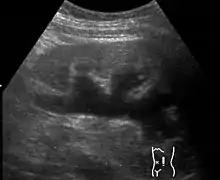

Renal ultrasonography of hydronephrosis caused by a left ureteral stone.

Imaging studies, such as an intravenous urogram (IVU), renal ultrasonography, CT, or MRI, are also important investigations in determining the presence and/ or cause of hydronephrosis. Whilst ultrasound allows for visualisation of the ureters and kidneys (and determine the presence of hydronephrosis and / or hydroureter), an IVU is useful for assessing the anatomical location of the obstruction. Antegrade or retrograde pyelography will show similar findings to an IVU but offer a therapeutic option as well. Real-time ultrasounds and Doppler ultrasound tests in association with vascular resistance testing helps determine how a given obstruction is effecting urinary functionality in hydronephrotic patients.[9]

Kay recommends that a neonate born with untreated in utero hydronephrosis receive a renal ultrasound within two days of birth. A renal pelvis greater than 12mm in a neonate is considered abnormal and suggests significant dilation and possible abnormalities such as obstruction or morphological abnormalities in the urinary tract.[9]